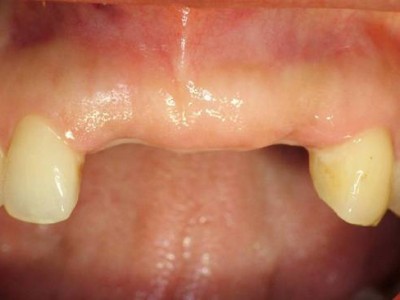

A+ 임플란트의 다양한 케이스를 확인해보세요.